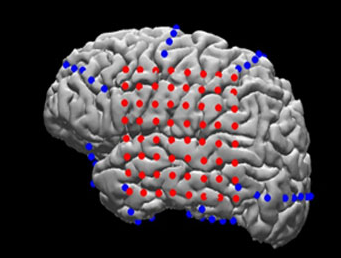

电极可置于硬脑膜外(硬膜外)或硬脑膜下(硬膜下)。条状或网格状电极覆盖了皮质的大面积区域(从4到256个电极)[2],从而可以进行各种各样的认知研究。

图中:病人大脑的MRI重建,电极覆盖(红色:网格阵列;蓝色:条带阵列),

使神经生理活动与神经解剖结构精确匹配(图片来自:Yang et al.,Neuroimage,2012)